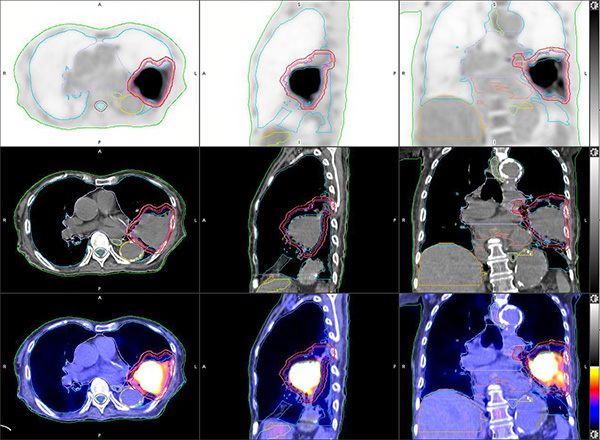

正电子/电脑双融扫描模拟定位 (PET/CT Sim) 为放射治疗疗程规划提供一站式新陈代谢评估及电脑扫描模拟定位 (CT Sim) 。放射治疗达到最佳效果的关键, 在於对肿瘤释放最大剂量的辐射及令健康组织免受损害。正电子/电脑双融扫描正好利用多样化正电子示踪剂,清晰地呈现目标肿瘤的新陈代谢变动丶量化其入侵性及定性其组织功能状态(如细胞分化及缺氧)。

部门的正电子/电脑双融扫描器配备SiPM技术,并外置激光定位系统及平面指标托板,可进行精准的同步空间配准及高解像度造影。一体化的正电子/电脑双融扫描数据 能 简化评估及模拟定位程序,为病人度身订造治疗方案。正电子扫描影像中的资讯(如肿瘤生物形态及功能数据)直接与电脑扫描定位影像整合,可用作计算及增加辐射剂量之用,更同时适用於 治疗前及治疗期间的中段评估 及 进行适应性放射治疗。